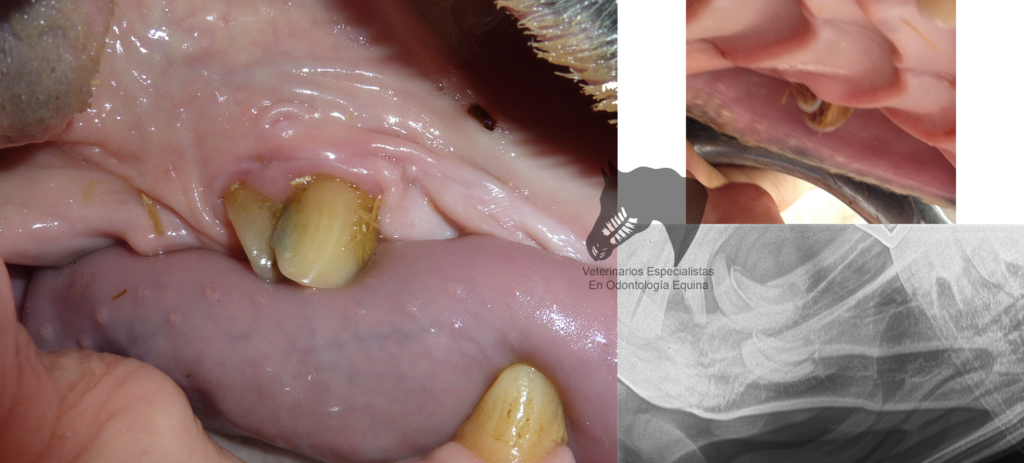

Es fundamental tener en cuenta que el cuidado dental adecuado es crucial para garantizar la salud bucal del lobo. Esto implica realizar visitas regulares al veterinario especializado en odontología animal, realizar limpiezas profesionales periódicas y proporcionar una alimentación equilibrada que favorezca la salud dental.